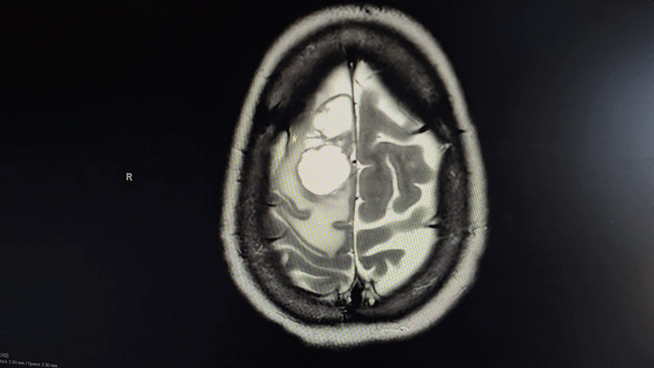

Just as we thought it was under control and hoping she was in the clear, she started having headaches that turned into severe brain fog and clumsiness. She was scheduled for a brain MRI, but before it could happen, she suffered a seizure on Halloween morning 2025 and was rushed to the emergency room. The devastating news: the cancer had metastasized to her brain. She underwent successful brain surgery on November 3, 2025, to remove the two tumors, but the damage from the tumors, swelling, seizure, and surgery has left her in a compromised state. She now has very limited mobility on her left side and we are still learning the full extent of the cognitive impact.